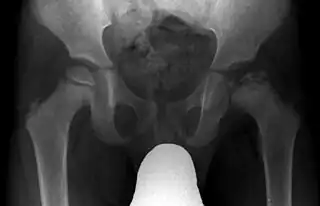

![]() Imagen radiográfica anteroposterior de la cadera de un paciente con enfermedad de Legg-Calvé-Perthes | ||